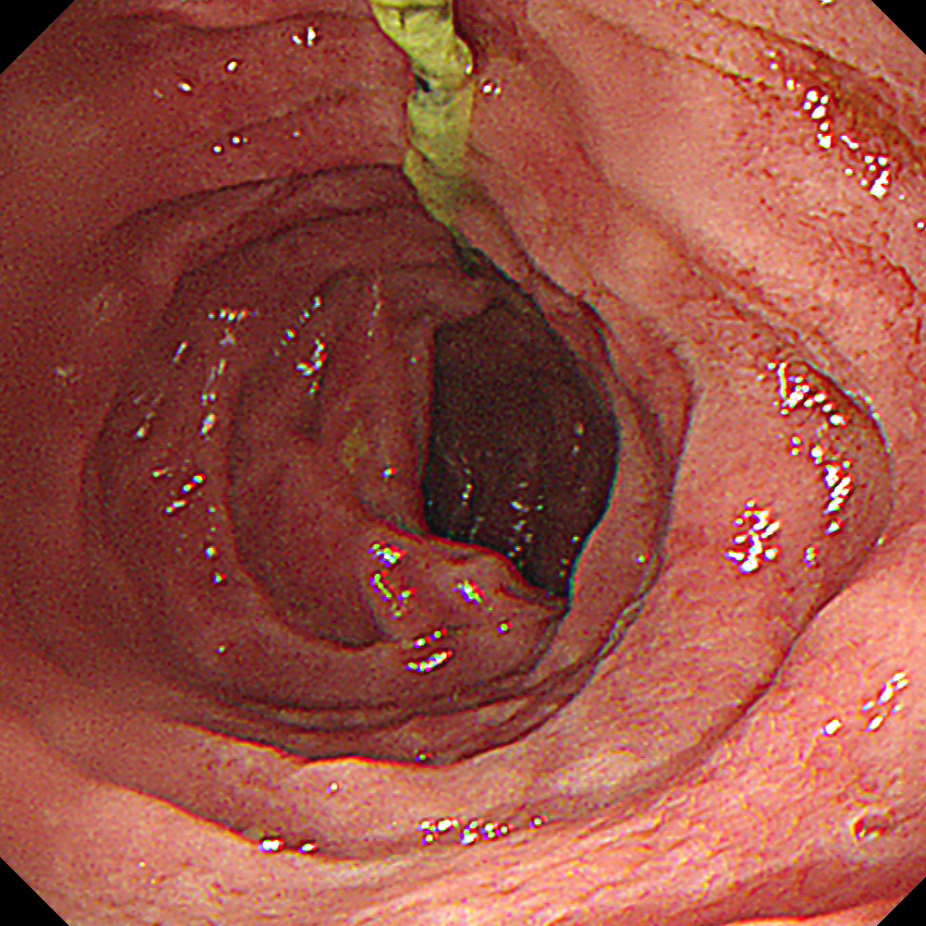

医生随即为她安排胃镜检查,屏幕上清晰显示出一颗椭圆形果核,表面被消化液浸润得异常光滑,像一颗 「涂了油的玻璃球」。

消化内科熊娇燕主任医师盯着屏幕分析道,这颗 2×2.5 厘米的果核不仅体积大、外形浑圆、质地坚硬,最麻烦的是表面光滑得几乎无处着力。「这类异物难靠胃肠蠕动排出,滞留过久或强行推送可能引发肠梗阻,那时就不得不做开腹手术。」

情况紧急,熊娇燕团队决定圈套器取出。她紧盯屏幕、精准下手,顺着果核长径套牢,让它以最小截面对准食管,慢慢调整力度回撤。